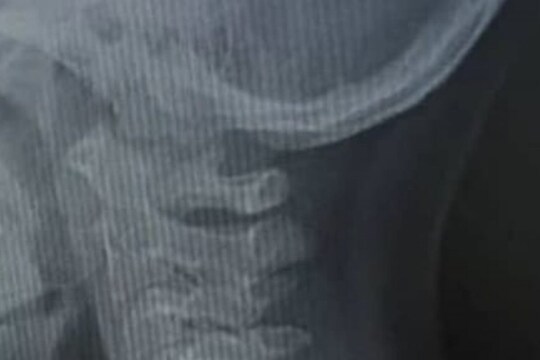

नवी दिल्ली 30 मार्च : लहान मुलं निरागस असतात. त्यांना समोर दिसणारी प्रत्येक गोष्ट खेळण्यासाठीच असते, असं वाटतं. अशा परिस्थितीत पालकांना खूप जबाबदारीने वागावं लागतं. त्यांना यावरही विशेष लक्ष ठेवावं लागतं, की त्यांच्या मुलांच्या आजूबाजूला अशी कोणतीही धोकादायक गोष्ट नाही ज्यातून त्यांना काही नुकसान पोहोचेल. अलीकडेच सोशल मीडियावर (Social Media) एका डॉक्टरने त्यांच्याकडे आलेली एक केस ट्विटरवर शेअर केली. यामागचं कारणही त्यांनी स्पष्ट केलं. याबद्दल माहिती देऊन त्यांना इतर पालकांनाही सावध करायचं आहे. प्रेयसीचं लोकेशन ट्रॅक करण्यासाठी केली हद्द पार; अशा ठिकाणी बसवलं Apple Watch की पोलसही हैराण ट्विटरवर डॉ. मोहम्मद शैफुल यांनी त्यांच्या सात वर्षांच्या रुग्णाचा एक्स-रे रिपोर्ट शेअर केला आहे. वेळीच योग्य उपचार झाले नसते तर मुलाचा मृत्यू झाला असता. या मुलाने पन्नास पैशाचं एक नाण गिळलं होतं (Boy Swallowed Coin), जे थेट त्याच्या अन्ननलिकेत अडकलं होतं. डॉक्टरांच्या म्हणण्यानुसार, ते दुसऱ्या वाहिनीत अडकलं असतं तर मुलांचे प्राण वाचले नसते.

या प्रकरणाची संपूर्ण माहिती देताना डॉ. शैफुल म्हणाले की, त्यांच्या वैद्यकीय अधिकाऱ्याने त्यांना सांगितलं होतं की, एका मुलाला आपत्कालीन स्थितीत दाखल करण्यात आलं आहे. मुलाने नाणं गिळलं होतं आणि त्याची प्रकृती चिंताजनक होती. हे समजताच डॉक्टरांनी प्रथम त्याच्या श्वासोच्छवासाच्या पद्धतीची माहिती विचारली. त्यानंतर त्याचा एक्स-रे रिपोर्ट मागवला. अहवाल पाहिल्यानंतर त्यांना संपूर्ण प्रकरण समजलं. काळजाचा ठोका चुकवेल हे दृश्य; कधीच पाहिला नसेल इतका खतरनाक Bike Stunt Video वैद्यकीय अधिकाऱ्यांनी सांगितलं की, मुलाची प्रकृती स्थिर आहे. त्याच्या अन्ननलिकेत काहीतरी अडकलं होतं. डॉ.शैफुल यांनी अहवाल पाहिल्यावर त्यांना समजलं की, ही अडकलेली वस्तू प्रत्यक्षात एक नाणं आहे. सुदैवाने नाणं श्वासनलिकेत न अडकता अन्ननलिकेत अडकलं होतं. नाणं श्वासनलिकेत अडकलं असतं तर या मुलाला श्वास घेता आला नसता. अडकल्यास. यामुळे त्याचा मृत्यूही होऊ शकत होता. डॉक्टरांनी तात्काळ शस्त्रक्रिया करून नाणं बाहेर काढलं. मुलाची प्रकृती आता स्थिर असून तो बरा होत आहे.